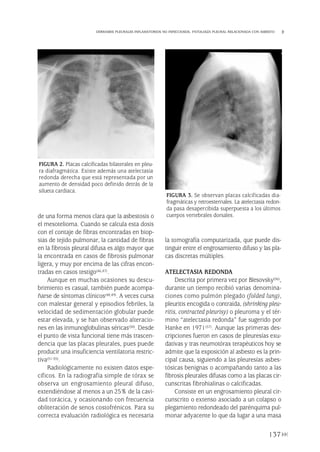

En la radiografía de tórax las placas pleu-

rales relacionadas con la exposición al asbes-

to aparecen casi exclusivamente en la pleura

parietal y pueden calcificarse (10%). Su valor

predictivo es del 79%, frente al 100% de la

TAC de alta resolución (TACAR). Se localizan

bilateral y posterolateralmente, en los márge-

nes inferiores de las costillas y en la superfi-

cie diafragmática (Fig. 2). Si son unilaterales

FIGURA 2. Placas pleurales bilaterales posteriores:

TAC.